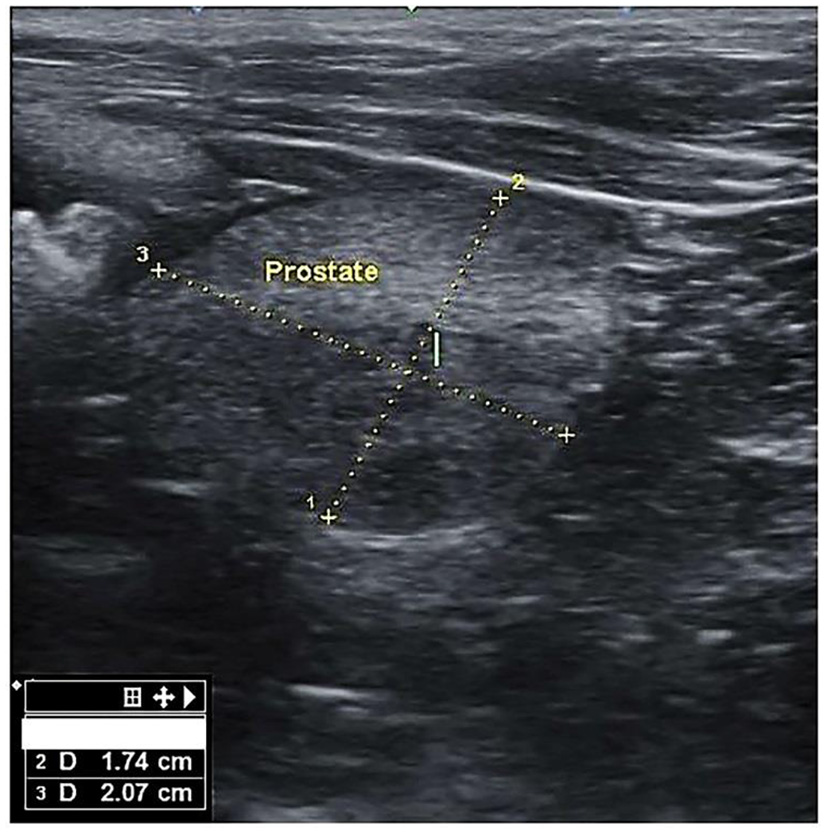

There mainly were symmetrical enlargements and homogeneous parenchyma in the prostates of dogs in BPH dogs (Figure 1). The prostate of some cases (n = 3) was asymmetric and heterogeneous because of intraparenchymal cysts and nodules in the ultrasound evaluation, and these cases were excluded from the study. There were no visible changes in the prostate parenchyma in the B group. Group A included six mongrels and 18 other dogs from six defined breeds, i.e., Terrier (n = 10), Siberian Husky (n = 3), Spitz (n = 2), German Sphered (n = 1), Belgian Malinois (n = 1), and Pekingese (n = 1). The weight ranged from 3 to 55 kg, with a median of 8.30 kg (interquartile range [IQR]: 6.1–16). Age ranged from 4 to 15 years, with a median of 6.0 years (IQR: 5.25–7.75). Group B included three mongrels and eight other dogs from five defined breeds, i.e., Shih tzo (n = 3), Terrier (n = 2), German Sphered (n = 1), Pekingese (n = 1), and Pomer (n = 1). Weight ranged from 4.5 to 30 kg, with a median of 7.0 kg (IQR: 4.5–30.0). Age ranged from 4.5 to 10 years, with a median of 5.50 years (IQR: 5.0–7.5).

Figure 1

Transverse section of the prostate gland in dogs suffering from BPH, showing the height (1) and width (2).